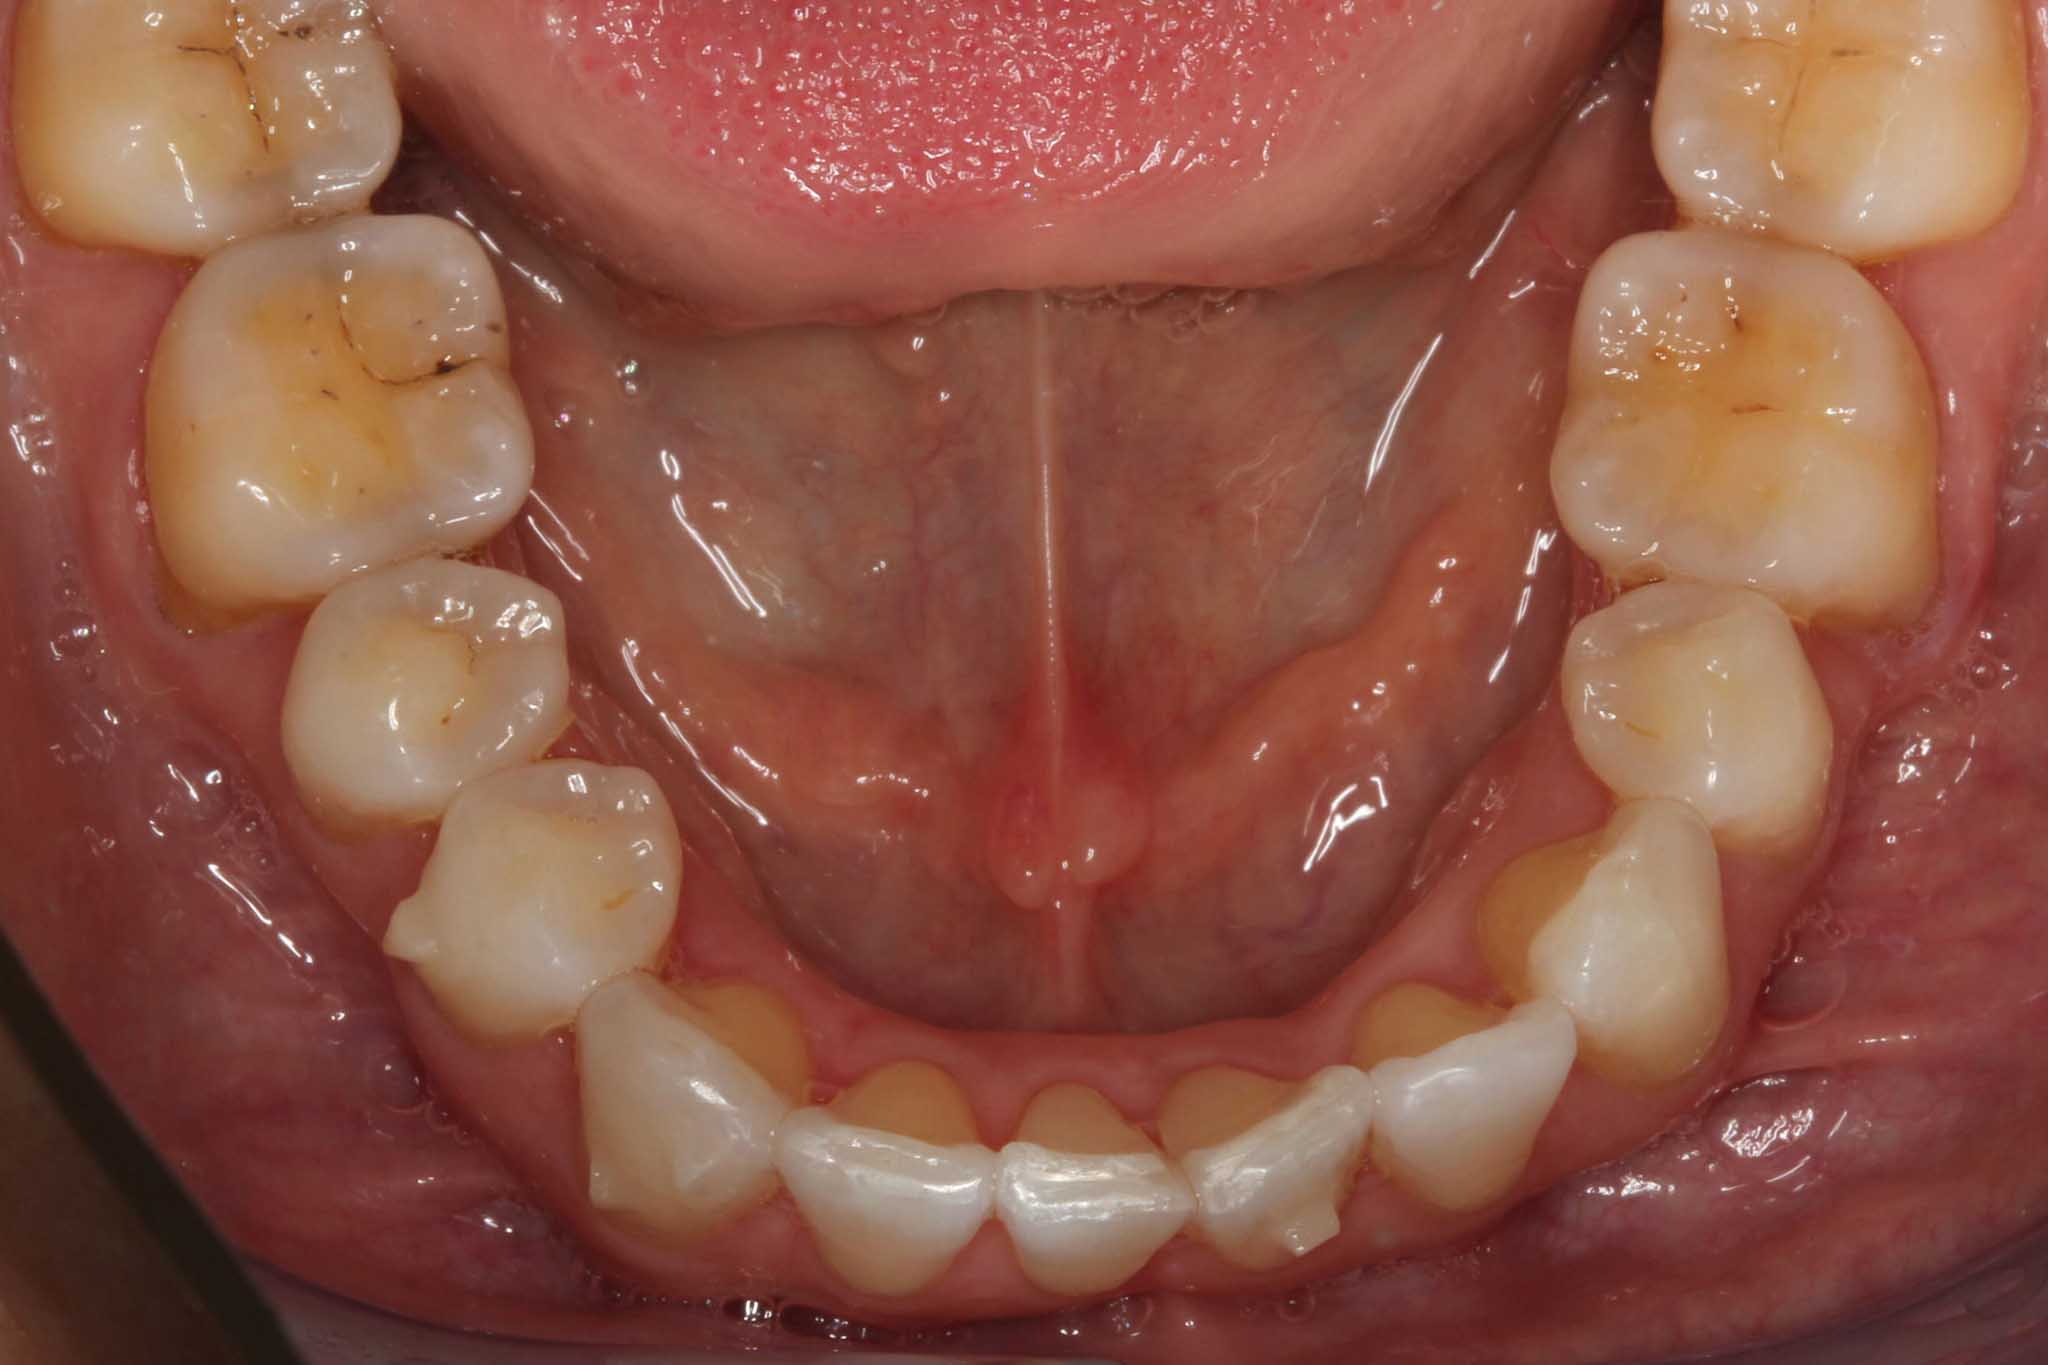

Før- og etterbilder – Resultater fra retainerbehandling

Flere bilder